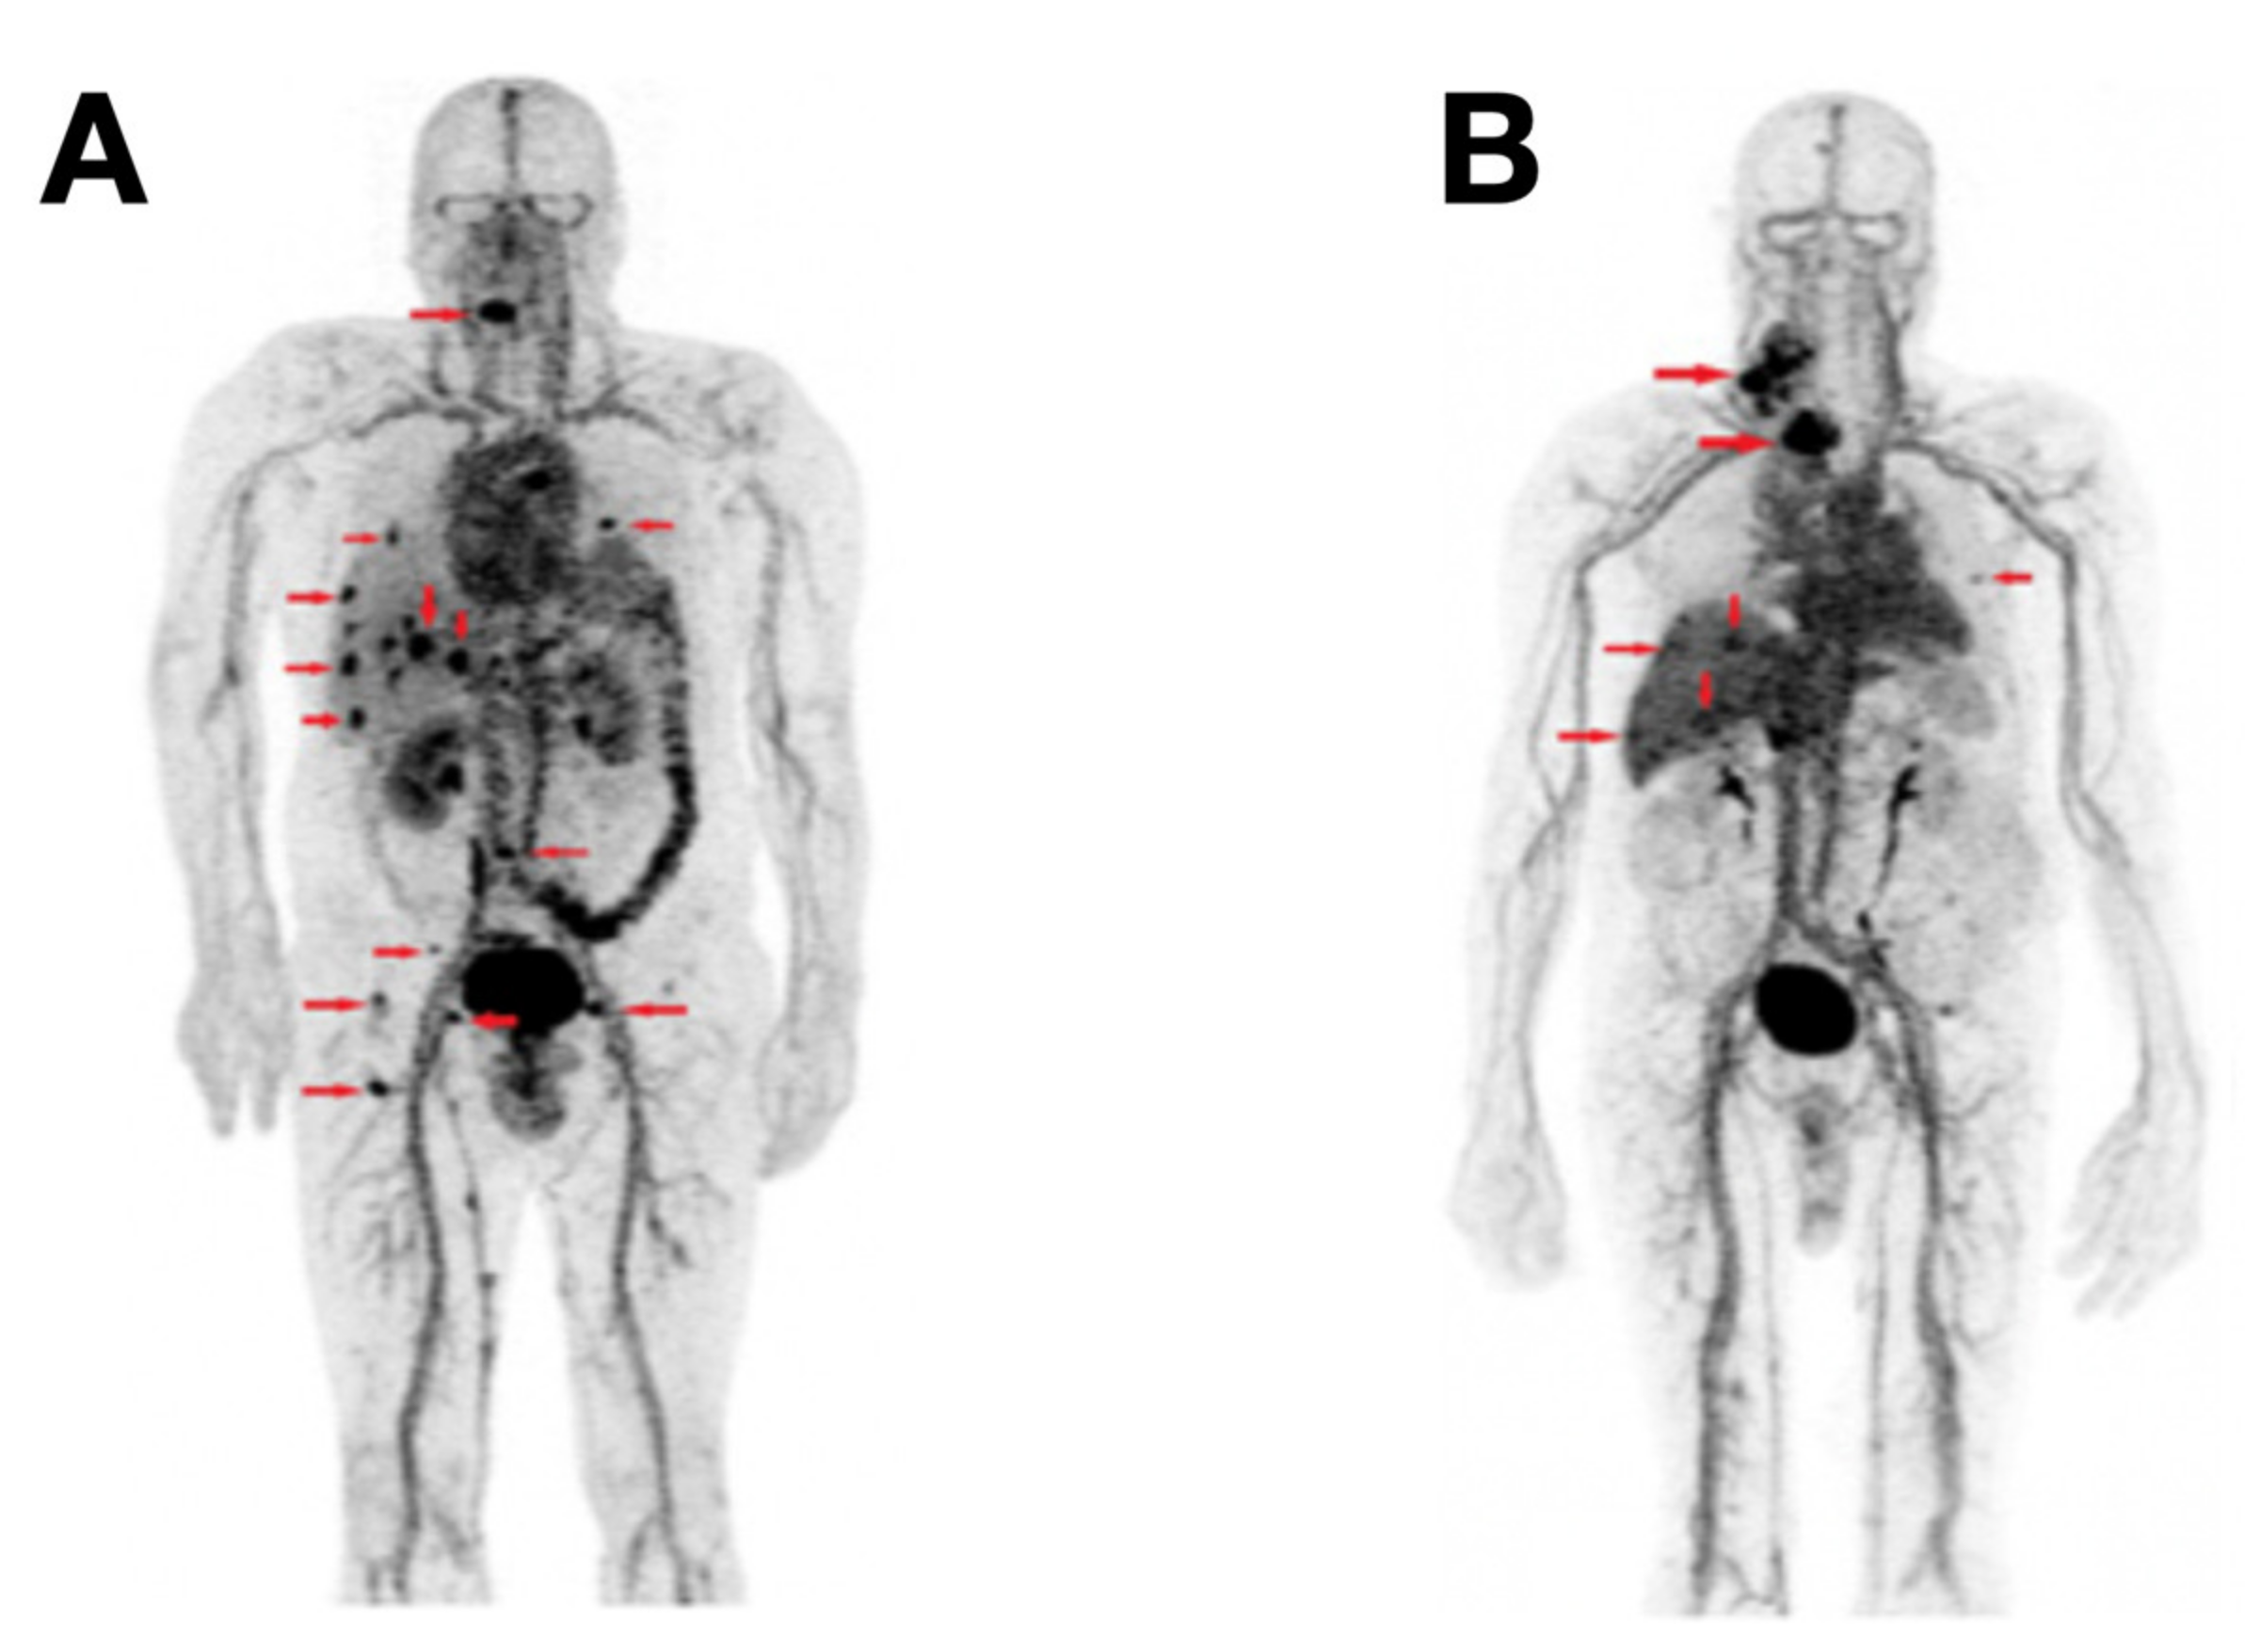

- Bodet-Milin, C.; Faivre-Chauvet, A.; Carlier, T.; Rauscher, A.; Bourgeois, M.; Cerato, E.; Rohmer, V.; Couturier, O.; Drui, D.; Goldenberg, D.M.; et al. Immuno-PET Using Anticarcinoembryonic Antigen Bispecific Antibody and 68Ga-Labeled Peptide in Metastatic Medullary Thyroid Carcinoma: Clinical Optimization of the Pretargeting Parameters in a First-in-Human Trial. J. Nucl. Med. 2016, 57, 1505–1511. [Google Scholar] [CrossRef] [Green Version]

- Bodet-Milin, C.; Bailly, C.; Touchefeu, Y.; Frampas, E.; Bourgeois, M.; Rauscher, A.; Lacoeuille, F.; Drui, D.; Arlicot, N.; Goldenberg, D.M.; et al. Clinical Results in Medullary Thyroid Carcinoma Suggest High Potential of Pretargeted Immuno-PET for Tumor Imaging and Theranostic Approaches. Front. Med. 2019, 6, 124. [Google Scholar] [CrossRef]